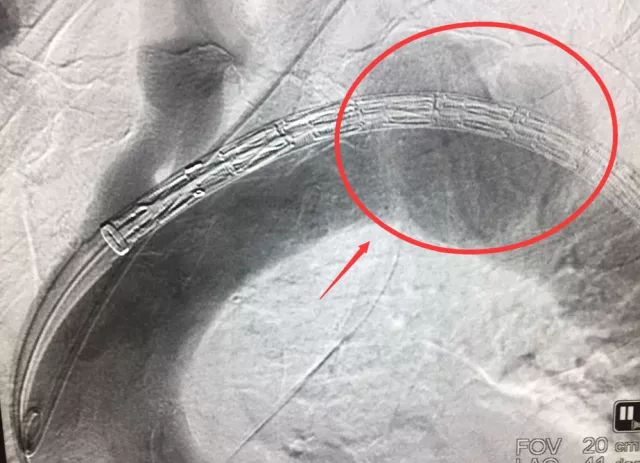

術中造影影像可以清晰地看到主動脈瘤“消失”的過程

如何解決,王主任想到了上海九院血管外科的創(chuàng)新技術—“激光原位開窗”。由于主動脈復雜的解剖結構和分支的變異性,在胸主動脈腔內修復術中,主動脈主要分支的血運重建是非常復雜的。而激光原位開窗術,則是通過結合多項技術,運用激光在覆膜支架的膜上打孔開窗,恢復諸如張大爺這樣受到支架影響的鎖骨下動脈的血流。

通過瑞慈醫(yī)院上海名醫(yī)中心,瑞慈醫(yī)院心臟血管外科請來了上海九院的專家進行指導,經過嚴格的會診、術前討論和精心準備,醫(yī)生為張大爺在局麻條件下進行了腔內主動脈支架植入及激光原位開窗手術。術后轉入ICU進行過渡,一天后就轉回了普通病房。利尿,降血壓,調節(jié)電解質,改善心功能,補充蛋白質,張大爺恢復平穩(wěn),順利出院。